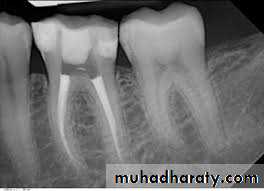

Endodontic infections can be classified according to the anatomic location as intraradicular or extraradicular infection.Intraradicular infection is caused by microorganisms colonizing the root canal system and can be subdivided into three categories according to the time microorganisms entered the root canal system: primary infection, caused by microorganisms

that initially invade and colonize the necrotic pulp tissue (primary or initial or “virgin” infection);

PRIMARY INTRARADICULAR INFECTIONMicrobial Composition and Diversity

Primary infections are characterized by a mixed (multispecies) community conspicuously dominated by anaerobic bacteria. The number of bacterial cells may vary from 10³ to 10⁸ per root canal with a mean of 10 to 20 species/phylotypes per infected canalThe size of apical periodontitis lesion has been shown to be proportional to the number of bacterial species and cells in